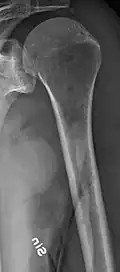

The diagnostic examination of a person with suspected multiple myeloma typically includes a skeletal survey. This is a series of X-rays of the skull, axial skeleton, and proximal long bones. Myeloma activity sometimes appears as "lytic lesions" (with local disappearance of normal bone due to resorption) or as "punched-out lesions" on the skull X-ray ("raindrop skull"). Lesions may also be sclerotic, which is seen as radiodense.[76] Overall, the radiodensity of myeloma is between −30 and 120 Hounsfield units (HU).[77] Magnetic resonance imaging is more sensitive than simple X-rays in the detection of lytic lesions. An MRI may supersede a skeletal survey, especially when vertebral disease is suspected. Occasionally, a CT scan is performed to measure the size of soft-tissue plasmacytomas. Nuclear Medicine Bone scans are typically not of any additional value in the workup of people with myeloma (no new bone formation; lytic lesions not well visualized on nuclear bone scan).

Multiple myeloma in the upper arm -

Femur with multiple myeloma lesions -

Same femur before myeloma lesions for comparison -